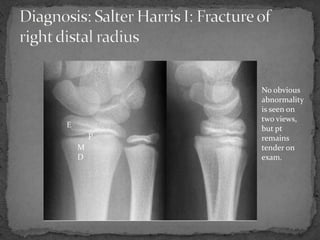

A 9 year old female presented to the emergency department after falling from a horse at summer camp and injuring her right wrist. She complained of pain with palpation and movement of the wrist. Examination revealed mild swelling and tenderness over the wrist, but plain films did not show any obvious abnormalities. Due to the possibility of a Salter Harris I fracture that may not be visible on initial x-rays, the patient was splinted and advised to follow up with orthopedics in 7-10 days for repeat films to check for any delayed findings.